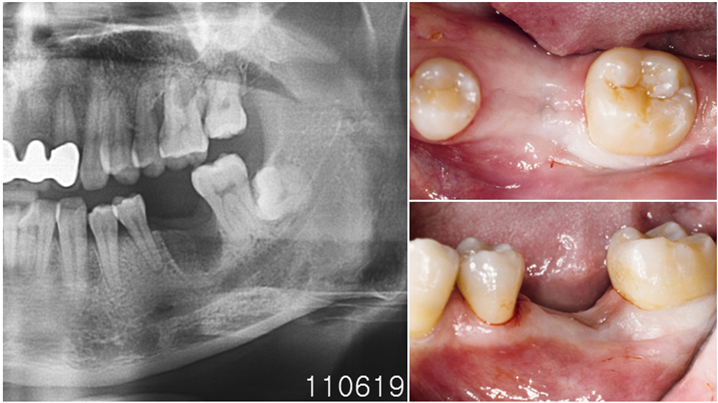

Clinical case: Single molar implant with bone augmentation

- Courtesy of Dr. Jung Sam Lee, Korea -

AnyOne, bone augmentation, osteotomy socket, peri-implant tissue, autogenous bone, GBR, single replacement, Auto-Max, Dr. Jung Sam Lee

AnyOne implant system, Auto-Max

“AnyRidge implant enables fast and stable

osseointegration at this extreme case of bone defect. ”

Clinical case: Bone filling into the bottom of deepest thread at 8.0mm AnyRidge fixture

- Courtesy of Dr. Kwang Bum Park -

AnyRidge, Knifethread ,extraction socket, ,initial stability ,Allograft, ,osseointegratio ,Dr. Kwang Bum Park, , Mandibular, Single replacement, AnyRidge, Mega-oss,

Implant system-AnyRidge, Regeneration-Mega-Oss